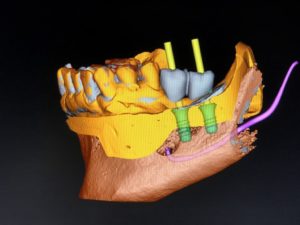

La TAC dentale può essere richiesta per una valutazione più precisa degli spessori ossei in vista di una terapia riabilitativa con impianti.

La TAC è un’indagine elettiva che deve essere eseguita solo in caso di reale necessità. In molti casi un chirurgo esperto riesce a formulare una diagnosi corretta e a programmare un’altrettanto valida terapia basandosi sull’analisi di radiografie tradizionali quali panoramica o radiografie endorali.

Anche l’implantologia può essere programmata senza l’ausilio di un esame TAC quando l’esame clinico e radiografico tradizionale rivelino una buona situazione anatomica e la lontananza di strutture nobili (vasi o nervi) che potrebbero essere danneggiati durante l’atto chirurgico.

Negli ultimi anni il contenzioso medico-legale ha spesso spinto i medici ad una eccessiva prescrizione di esami che in realtà non erano necessari ed avevano l’unico ragione di evitare eventuali ricorsi da parte dei pazienti.